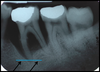

Comment mettre en évidence l’atteinte du niveau osseux

Seul l’examen radiographique permet de quantifier la perte osseuse et donc l’importance du déchaussement.

paro13

Destruction osseuse non comblée au cours de l’extraction

La perte osseuse est définitivement fixée